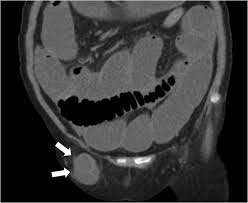

3. 대퇴부(femoral) 탈장

- 서혜부 아래쪽, **대퇴관(femoral canal)**을 통해 돌출되며, 주로 **여성에게 호발**합니다 :contentReference[oaicite:8]{index=8}.

- 허벅지 고관절부 근처에 작은 **볼록한 덩어리** 발생

- 줄었다 나타나거나 초기 통증은 약하지만, 진행되면 구역·구토·장폐색 증상 가능 :contentReference[oaicite:9]{index=9}.

- 응급 가능성이 높아, 통증·붓기 + 장폐색 또는 피부변색 등 동반 시 즉시 응급실 방문해야 합니다 :contentReference[oaicite:10]{index=10}.